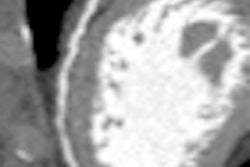

A growing body of evidence has demonstrated the value of coronary CT angiography (CTA) as an accurate, noninvasive modality to detect coronary artery stenoses and plaque, as well as predict future cardiac events. However, the small sample sizes used in many studies have limited their impact on public health policy, according to Dr. Hans-Christoph Becker and colleagues from Ludwig Maximilian University in Munich.

The results indicate CT-based findings of coronary plaque and stenosis are strong independent predictors of future cardiovascular events, Becker said at the ISCT conference.

The presence of significant coronary stenosis was associated with a tenfold higher risk for all cardiovascular events and a sixfold risk for death and unstable angina requiring hospitalization independent of coronary artery calcification, the researchers wrote in their study.

Becker pointed out during his presentation the results show there is a 4.5-fold risk associated with the presence of any coronary artery disease, and that each diseased coronary segment portends a 23% higher risk for adverse outcomes.